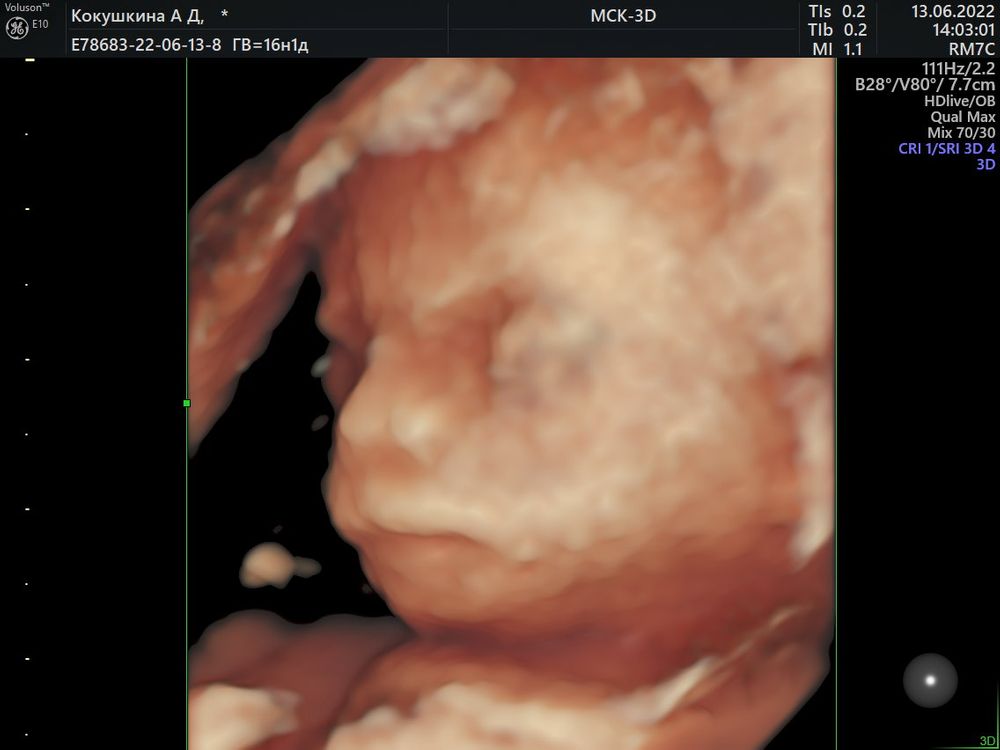

Узнали пол малыша в 16-17 недель🥰

Поздравляю вас!!! 💐 У нас на 1 скрининге почти такой же бугорок как у вас, в 12 нед 1д. Вы вселели в меня надежду, что есть шанс на мальчика😄

Поздравляюююю😍😍😍🌸🌸🌸 это уже 3 пост, где пишут, что по первому скринингу возможно девочка, по второму уже точно мальчик😂 у меня тоже так получилось🤗🤗🤗